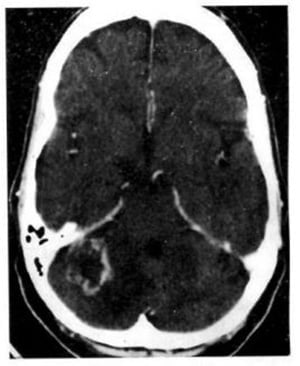

1.3. U nguyên bào tủy (Hình 1.58)

Dấu hiệu XQCLĐT:

– Điển hình ở thùy nhộng tiểu não, thường có mật độ hơi cao hơn nhu mô tiểu não bình thường. Bắt chất cản quang rõ trừ khi hoại tử.

– Não úng thủy do tắc nghẽn não thất 4.

– Di căn theo khoảng dưới nhện.

Hình 1.58. U nguyên bào tủy của thùy nhộng tiểu não ở trẻ 2 tuổi. Cắt lớp cách sau 10 tháng. Trước tiêm (a), dấu hiệu mơ hồ (mũi tên). Sau tiêm (b), một phần u bắt chất cản quang mạnh.